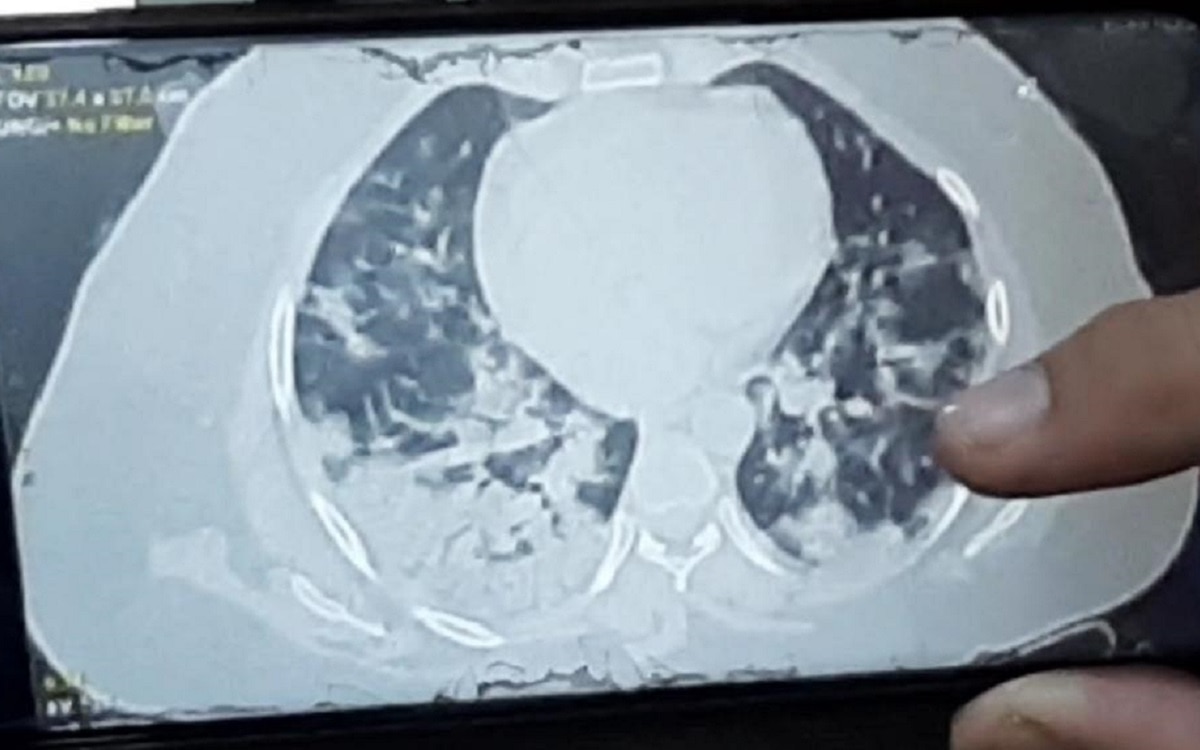

महिला 13 तारीख को खड़ी भी नहीं हो पा रही थी, सांस लेने में दिक्कत हुई तो चेक करने के बाद पता चला कि ऑक्सीजन लेवल 94 था. 13 तारीख को सिटी स्कैन करवाया तो उसके दोनों लंग्स में 80 परसेंट तक इंफेक्शन फैल चुका था.